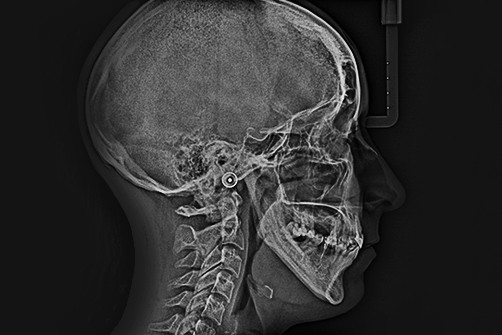

Chory po resekcji tkanek/narządów twarzoczaszki wymaga wnikliwej diagnostyki obrazującej zakres ubytku oraz stan podłoża kostnego. Wykonuje się zdjęcia radiologiczne RTG pantomograficzne szczęk OPG, konwencjonalną tomografię komputerową CT, stożkową tomografię komputerową CBCT, ukazującą trójwymiarowy obraz twarzoczaszki, oraz w razie potrzeby rezonans magnetyczny NMR. Możliwy jest również druk modeli 3D w skali 1:1 dowolnej części twarzoczaszki.

Diagnostyka ma za zadanie wykluczenie wznowy wyciętego nowotworu oraz pomoc w ocenie tkanki kostnej w okolicy ubytku. Ocena kości pozwala na zaplanowanie zabiegu wszczepienia implantów jako przyszłego fundamentu niezbędnego dla mocowania protez poresekcyjnych lub epitez twarzy.

Zastosowanie współczesnych technik obrazowania trójwymiarowego umożliwia precyzyjne zaplanowanie pozycji implantów czaszkowych, tak by ektoprotezę stabilnie osadzić na podłożu.